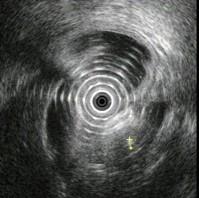

问题 图中胰腺病变可能的诊断是 ( )

选项 A、胰腺囊腺癌 B、胆总管结石 C、胰腺囊肿 D、慢性胰腺炎 E、正常

答案 D